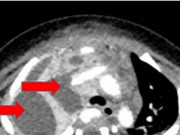

Bệnh nhi 7 tuổi bị sốt xuất huyết Dengue nặng kèm hội chứng thực bào máu hiếm gặp gây suy gan, suy thận nặng, phải thở máy và lọc máu liên tục.